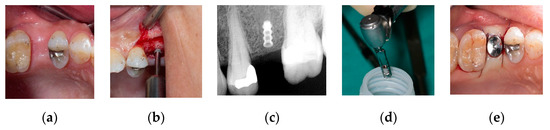

2.1.1. Surgical Procedure

Conventional Implant Placement